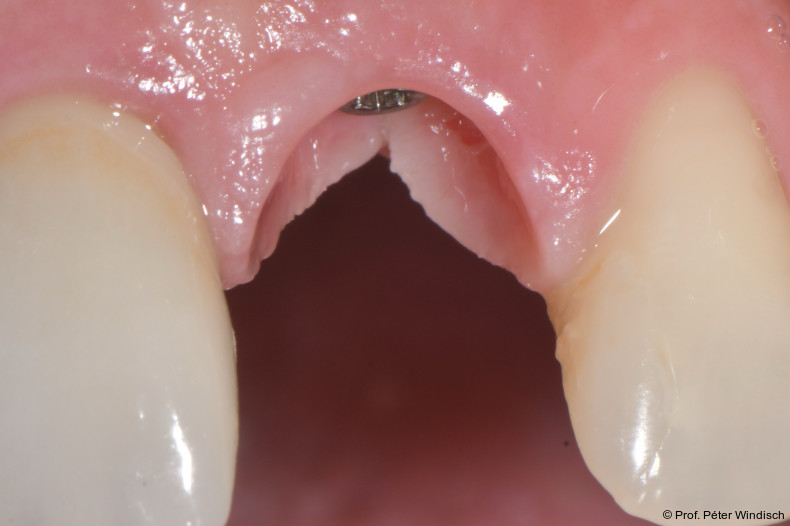

Der Patient wurde angewiesen, zwei Stunden lang nichts zu essen oder zu trinken, sowie für die nächsten 24 Stunden keine Zahnreinigung oder CHX-haltige Mundspüllösungen und für die nächsten zwei Tage keine Interdentalbürsten zu verwenden.  Bei der Reevaluation nach sechs Monaten zeigte sich eine deutliche Verbesserung der periimplantären Gewebesituation. (Abb. 10+11). Durch die Behandlung konnten die klinischen Parameter deutlich verbessert werden. Die periimplantäre Sondierungstiefe wurde signifikant auf ein physiologische Taschentiefe reduziert, es war zudem keine Blutung auf Sondierung (BOP) mehr vorhanden.

Das Weichgewebe präsentierte sich klinisch entzündungsfrei. Radiologisch zeigte sich nach zwölf Monaten eine deutliche Verbesserung der knöchernen Situation im Sinne einer Auffüllung des knöchernen Defekts (Abb. 12). Das Ergebnis konnte durch regelmäßige Implantat-Maintenancetermine stabilisiert werden. Abbildung 13 zeigt die ausgereifte periimplantäre Hartgewebesituation.